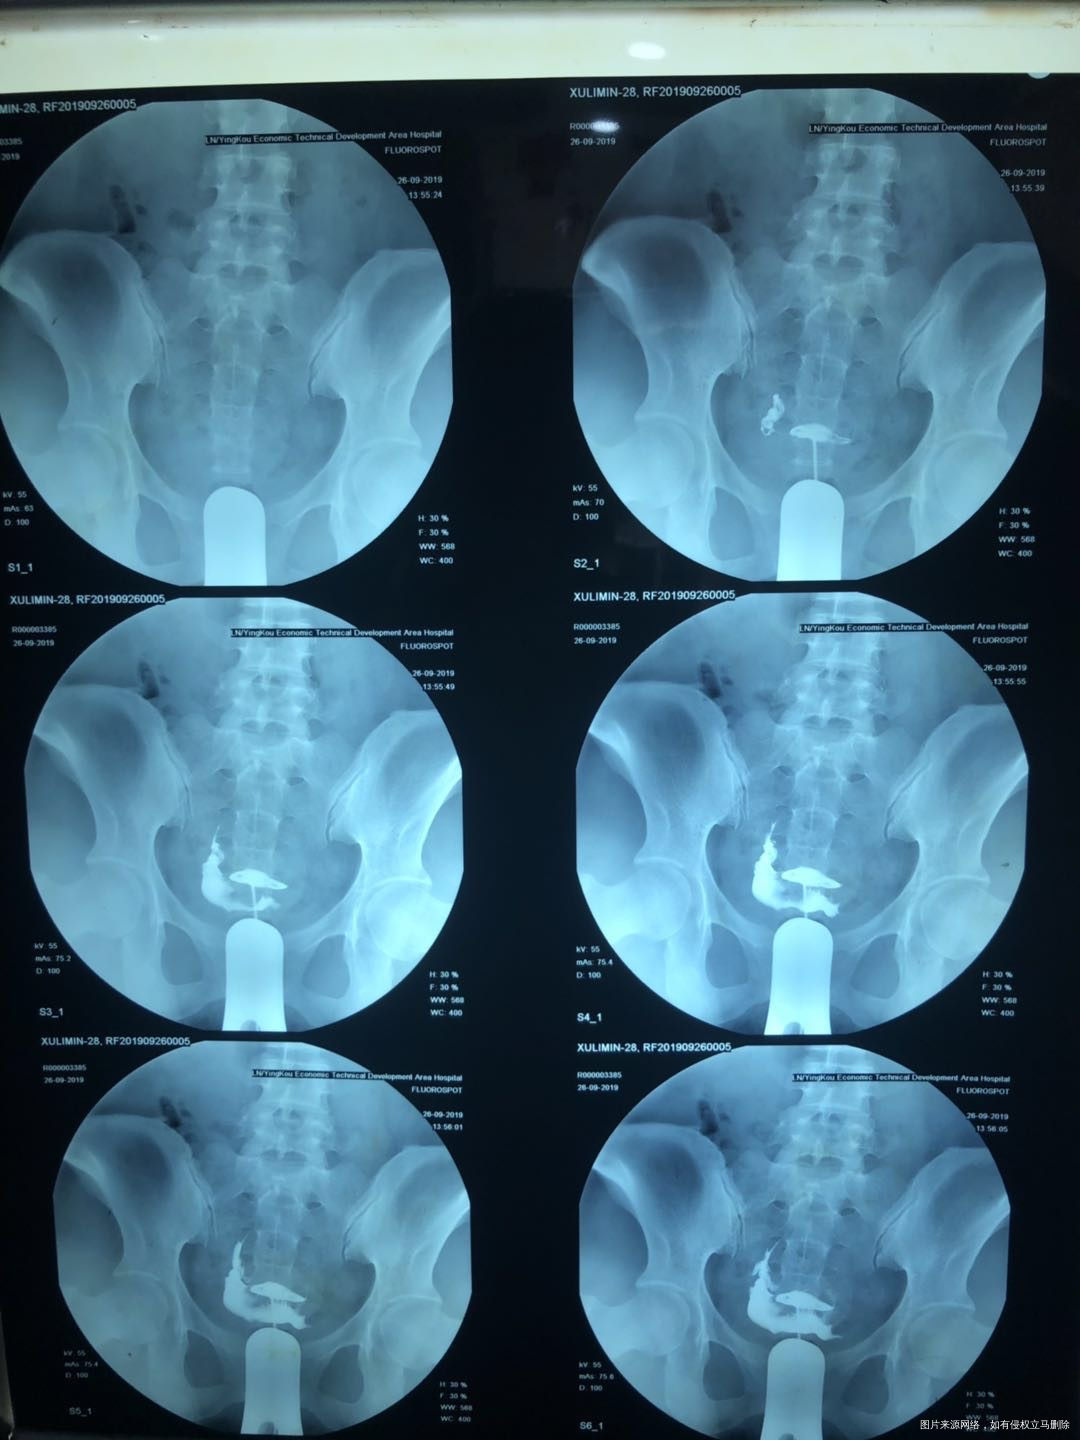

19年做的输卵管造影,之后做了几个月监测排卵一直未怀孕,想问下我这情况属于输卵管什么病症,适合怎么治疗

左侧输卵管完全梗阻,右侧看着还行,建议完善卵巢功能评估,月经期3-5天激素,甲功,amh,后根据卵巢功能看,如果卵巢功能还可以可以选择宫腹腔镜疏通后监测排卵,如果卵巢功能差,建议直接试管。

你好,根据你的造影片子来看左侧输卵管可能完全不通,右侧通的也不好,造影剂也盆腔内堆积,可能有盆腔炎症,这种情况不处理自然受孕的可能性低!建议完善夫妻双方检查,评估女方卵巢功能及男方精液情况,如果都是好的可以手术疏通双侧输卵管,然后尽快怀孕;或者直接试管婴儿助孕!

左侧完全不显影,完全梗阻,右侧也是欠佳,而且显影剂在那里堆积,显示一大片,应该是有炎症造成了粘连。估计右侧就是通的,也是通而不畅。你如果不想一步到位,直接试管婴儿技术助孕。那就先做个输卵管疏通术,同时治疗治疗盆腔粘连,自己先试着怀,半年后如果不行就转试管吧,这半年可以做卵泡监测指导同房,这样几率会大点!